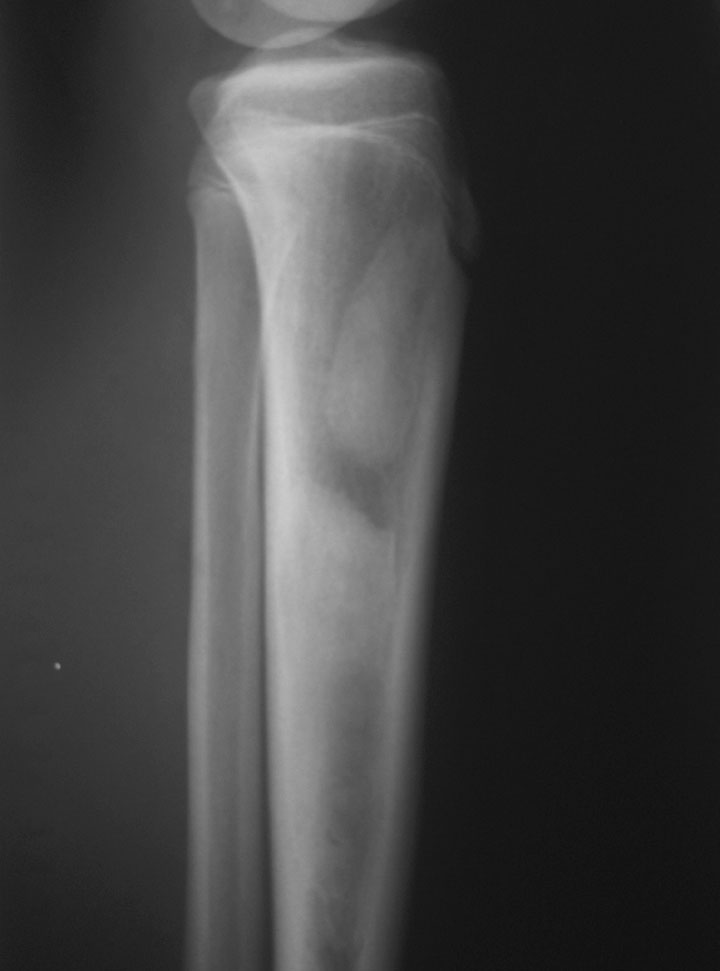

标题: CT19885:左胫骨上端肿瘤。 [打印本页]

标题: CT19885:左胫骨上端肿瘤。

男,20岁,医学院学生,11年前感左胫骨上端劳累后酸痛,曾由父母带到国内好几家有名望的医院诊治,但众说不一,所以基本上没有治疗。今年三月又开始出现症状,又到多家省级医院求治,但专家们的意见还是不能统一。各生化检查正常。mri考虑到胫骨上端良性血管瘤可能性大。ct考虑纤维瘤可能性大。请各位发表高见。

考虑左胫骨良性骨肿瘤或骨肿瘤样病变(多发性内生骨瘤?骨纤维结构不良?)。

考虑左胫骨良性骨肿瘤或骨肿瘤样病变(多发性内生骨瘤?骨纤维结构不良?)。骨梗死,纤维瘤。